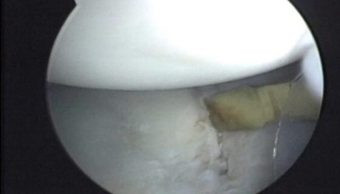

Durante la artroscopía se comprueba la existencia de la lesión de Hill Sacks, la cual es una lesión osteocondral por las luxaciones anteriores que ha sufrido el paciente